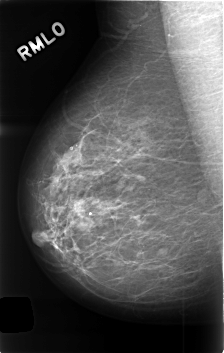

C_0408_1.RIGHT_MLO

RIGHT_MLO LINES 4584 PIXELS_PER_LINE 2904 BITS_PER_PIXEL 12 RESOLUTION 50 NON_OVERLAY